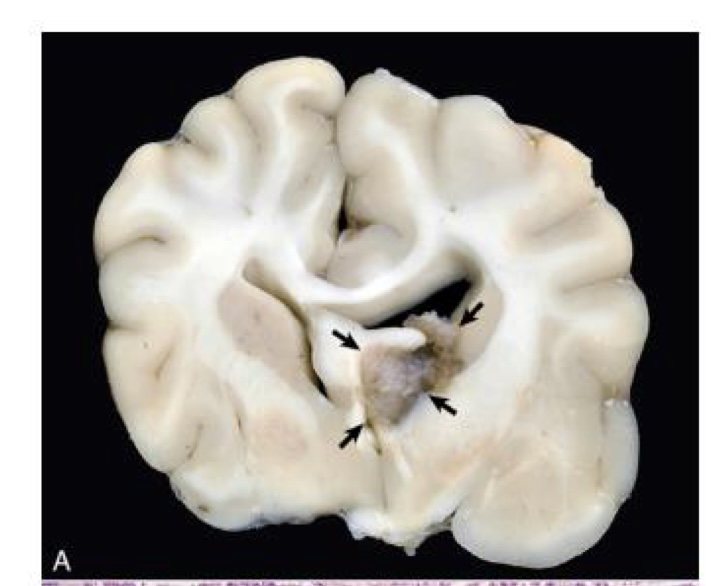

what is this?

astrocytoma

right hemisphere contains a poorly demarcated, nonencapsulated, expansile mass

lesion has displaced the midline to the left and compressed the right lateral ventricle